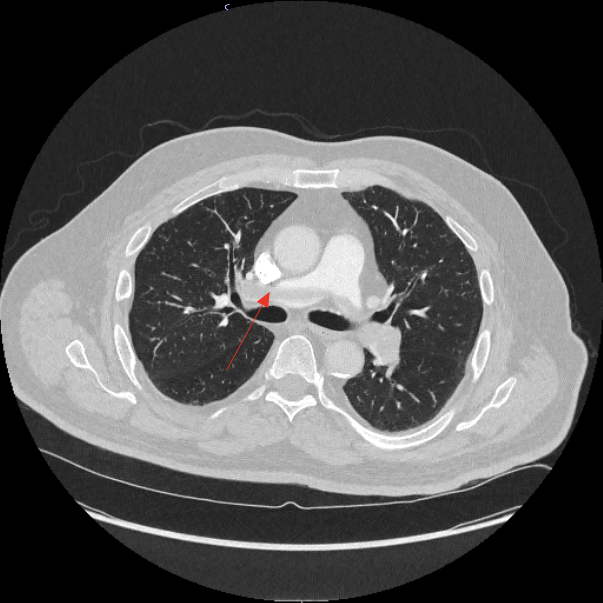

A day later, a non-contrast CT was ordered to evaluate the parenchymal lung disease as the source of dyspnea. Findings on imaging, as shown below in Figure 1, indicate a saddle pulmonary embolism. The subsequent CTA (Figures 1&2) showed the thrombus and contrast-enhanced imaging. In Figure 1, the attenuation differences between the clot and flowing blood in the pulmonary artery are seen. In Figure 2, the red arrow points to the saddle pulmonary embolism straddling the right and left pulmonary arteries.

Figure 2 Transverse CTA: red arrow points to.